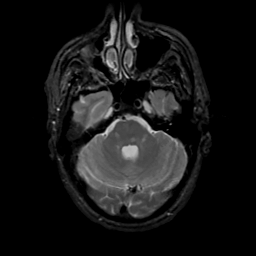

MR Study #16, June 23, 1991 -- Slice #13